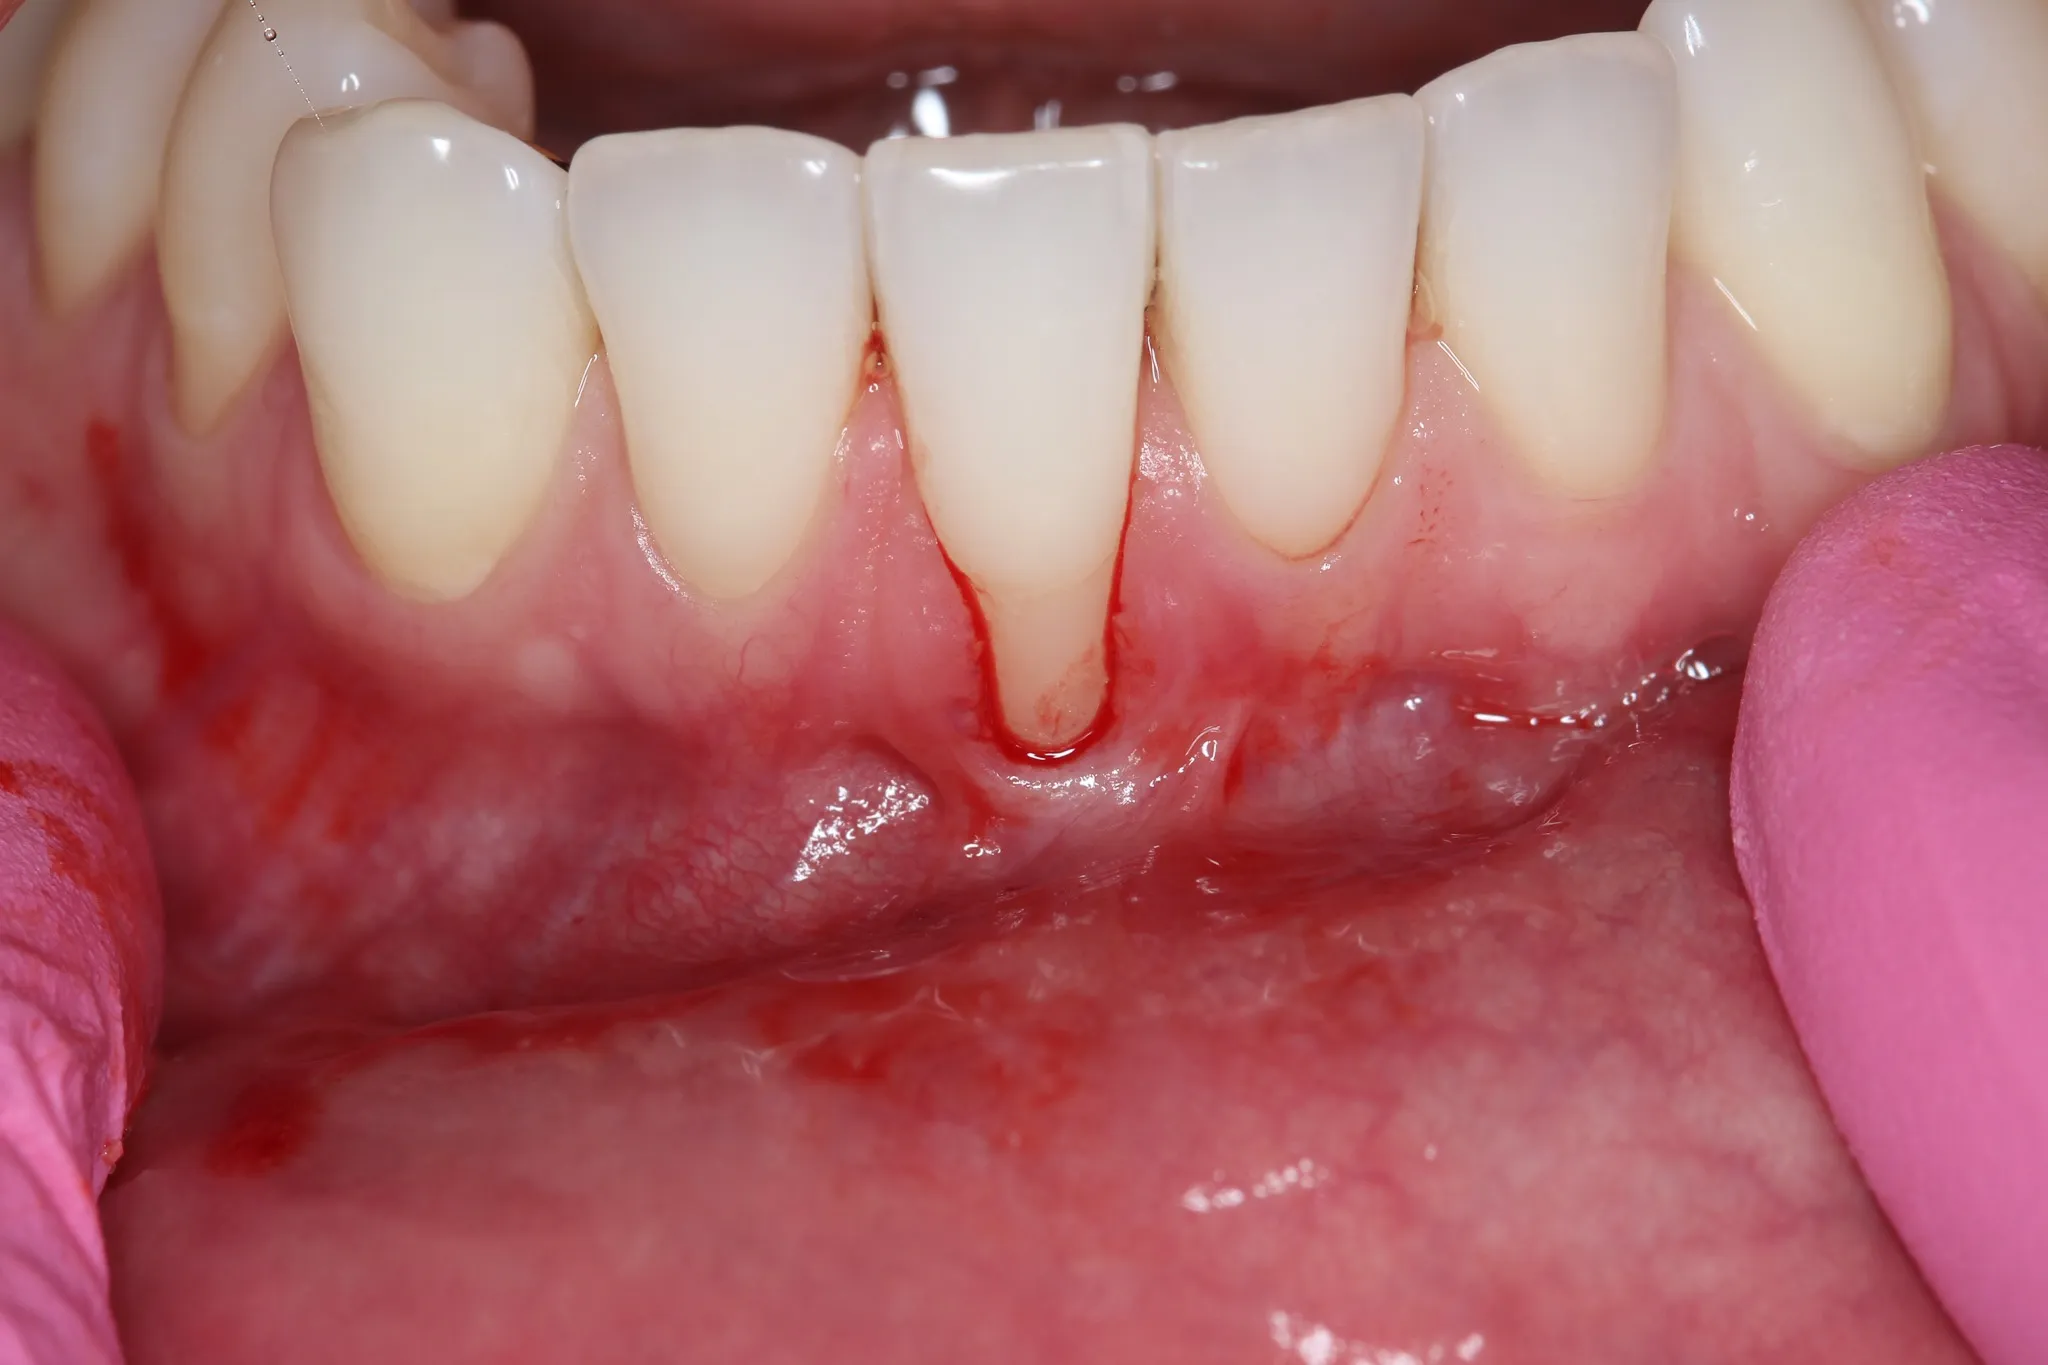

Gum Grafts

Restore receded gumlines and cover exposed tooth roots — eliminating sensitivity and protecting long-term dental health.